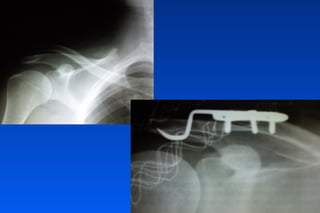

Placa Acromionclavicular

Fx Clavícula

Fx Clavicula: Criterios quirúrgicos

✓Fx abiertas

✓Hombro flotante

✓Pseudoartrosis

✓Interposicion de partes blandas

✓Compromiso neurovascular

✓Compromiso pleuropulmonar